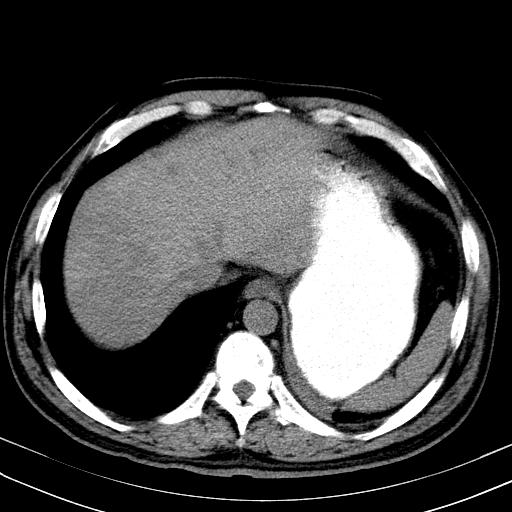

大家看看肝脏右叶片状低密度影是什么改变啊?

淋巴瘤?肝脏请增强后说啊

多发肿大淋巴结影,肝内改变需结合强化观察

多发肿大淋巴结影,肝内改变需结合强化观察。